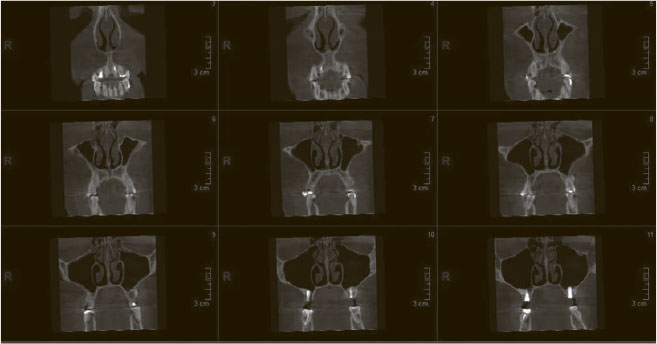

Это рентген 80 lvl. При помощи радиации безболезненно нарезает ваш череп на тоненькие слои (господин Пирогов говорит «Ма-ла-ца!» из мавзолея), по которым можно детально оценить состояние всех структур полости носа, их плотность, характер, взаиморасположение. Незаменимая процедура при хронических риносинуситах: позволяет решить вопрос о необходимости и объеме хирургического лечения. При острых осложненных проблемах дает понять, насколько все плохо.

Компьютерная томограмма придаточных пазух носа, фронтальная проекция